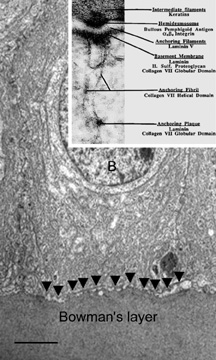

The cytoplasm of a corneal epithelial cell primarily contains cytoskeletal intermediate filaments and has sparse cytoplasmic organelles (i.e., mitochondria, endoplasmic reticulum, and golgi apparatus). The predominant cytoplasmic filament is keratin, whereas actin and microtubules are two other major types found in corneal epithelial cells. The epithelial cells are held together to one another by numerous anchoring junctions called desmosomes, whereas the basal surface of the epithelium adheres to the basal lamina and underlying Bowman's layer through aa adhesion complex composed of hemidesmosomes, anchoring fibrils (type VII collagen), and anchoring plaques (Fig. 4). The function of the corneal epithelium is twofold: (a) to form a barrier from the environment to the corneal stroma of the cornea, and (b) to form a smooth refractive surface on the cornea through interaction with the tear film.

Fig. 4. Transmission electron micrograph (10,000×) of a basal epithelial cell showing the adhesion complexes (arrowheads) that anchor it in place onto the Bowman's layer and summary inset. B, basal epithelial cell. Bar = 1 μm. (Inset from Albert and Jakobiec: Principles and practice of ophthalmology. Philadelphia, WB Saunders, 2000.)